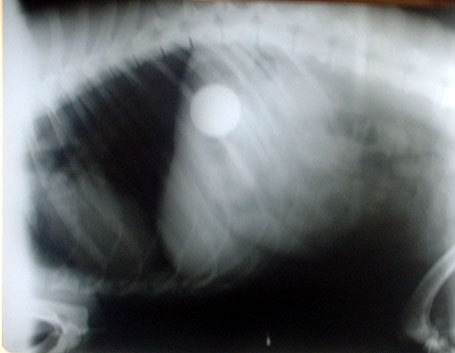

well here are the xrays. If you look at the white circle in the center that is the golf ball.